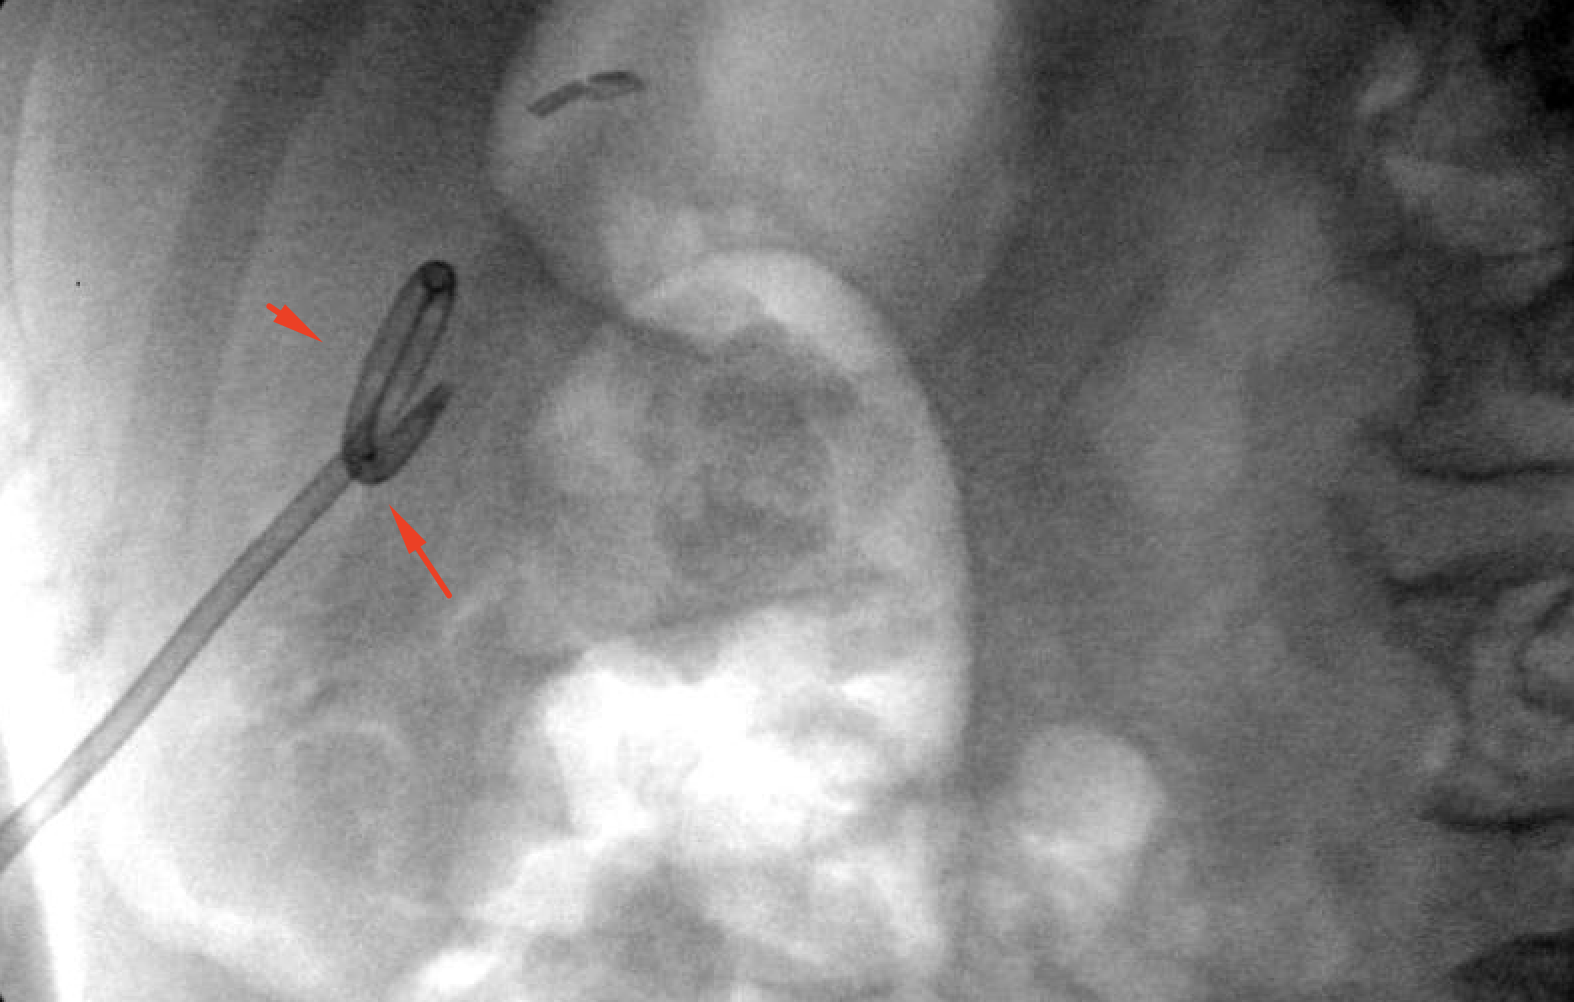

Age: 84

Sex: Male

Indication: Left-sided chest pain, recent cholecystectomy

Radiotracer: Tc99m mebrofenin (an iminodiacetic acid analog)

Sample ReportPositive for biliary leak, which is drained by the existing surgical drains.

No evidence of intra-abdominal bile collections.

No evidence of common bile duct obstruction.